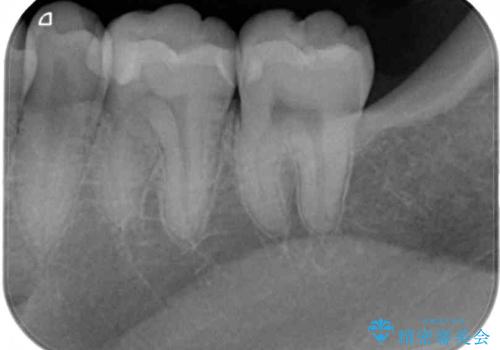

目視やレントゲン写真からは、以前処置された部分に大きな問題は認められませんでしたが、冷たい風をかけると強い痛みを感じる状態でした。

患者様と相談の上、詰め物を全て外した上でむし歯があるかどうかを確認し、セラミックインレーで精密な修復治療を行うこととしました。